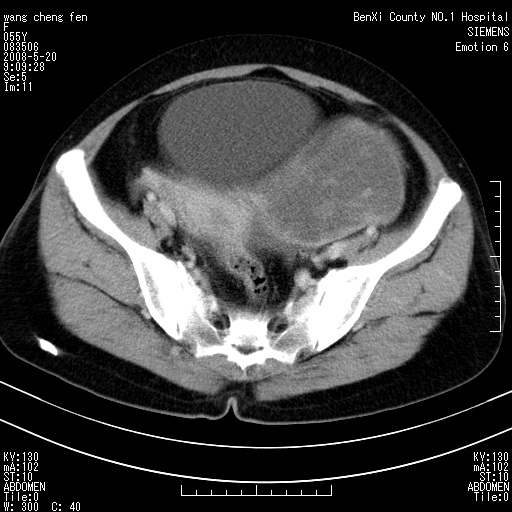

女、绝经后阴道流血3个月

左侧附件区巨大囊实性病灶,边缘光整,病灶囊壁较厚,增强示囊壁及实性部分明显强化,强化呈度与宫体实质大致相同,宫腔积液征像,未见盆腔积液等其他异常,考虑左侧卵巢囊腺癌,不除外囊腺瘤及浆膜下肌瘤坏死

左侧附件区巨大囊实性病灶,边缘光整,病灶囊壁较厚,增强示囊壁及实性部分明显强化,强化呈度与宫体实质大致相同,宫腔积液征像,未见盆腔积液等其他异常。绝经后阴道流血3个月,结合病史左侧卵巢囊腺癌首先考虑,宫腔扩大不除外累及。期待结果。

考虑巨大的浆膜下子宫肌瘤并变性坏死,宫颈周围静脉曲张。

1,宫颈部占位,宫颈癌?2,左侧附件区囊实性占位,界较清,实质部分强化明显。考虑浆膜下或阔韧带肌瘤囊变可能大。囊腺类肿瘤不除外。